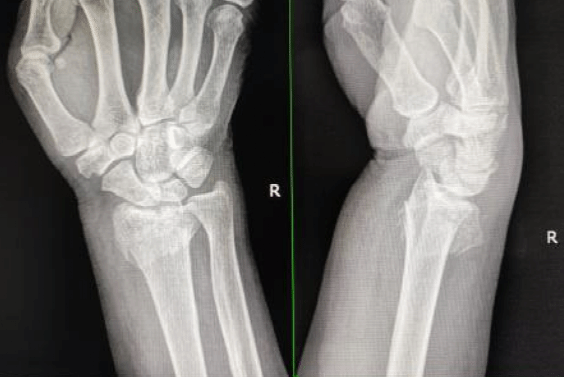

复位前外观及X片